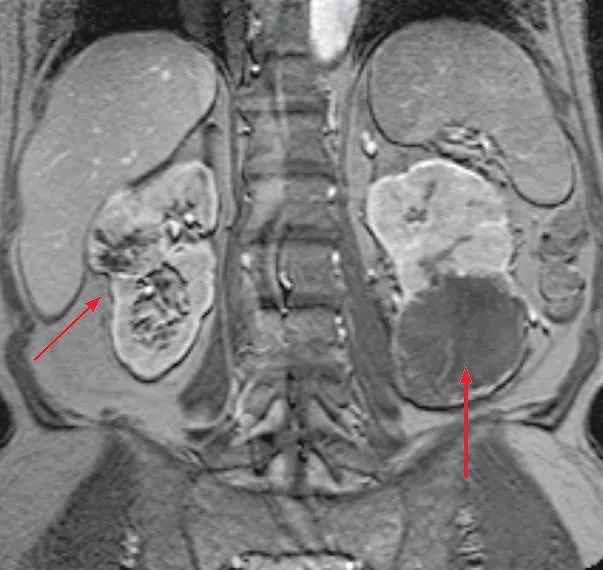

Tomografia komputerowa (TK) i rezonans magnetyczny (MRI): kiedy są zlecane?

Tomografia komputerowa (TK) i rezonans magnetyczny (MRI) to dwie zaawansowane techniki obrazowania, które dostarczają niezwykle precyzyjnych obrazów nerek i całego układu moczowego. Są one kluczowe w diagnostyce nowotworów nerek, pozwalając na dokładne określenie ich wielkości, lokalizacji i rozprzestrzeniania się. TK wykorzystuje promieniowanie rentgenowskie, natomiast MRI silne pole magnetyczne i fale radiowe. Oba badania pozwalają na bardzo dokładne zobrazowanie tkanek miękkich, co jest nieocenione w przypadku oceny guzów, torbieli złożonych, zmian zapalnych czy oceny naczyń nerkowych. Zlecane są, gdy USG nie daje pełnej odpowiedzi lub konieczne jest szczegółowe planowanie leczenia.